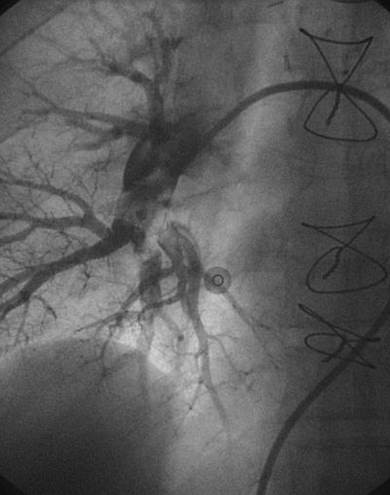

Angiografía de la arteria pulmonar izquierda realizada con un catéter en espiral de 6 F en ángulo, que demuestra la presencia de un trombo de gran tamaño dentro de la arteria pulmonar izquierda y en las bifurcaciones lobulares intermedia e inferior.

Se efectuó una trombectomía reolítica con el catéter PE de AngioJet® mediante un catéter guía multifunción de 8 F a través de una guía de angioplastia hidrófila de 0,035’’.

Angiografía pulmonar izquierda realizada tras una trombectomía reolítica en la que se muestra la mejora del índice de perfusión y obstrucción.